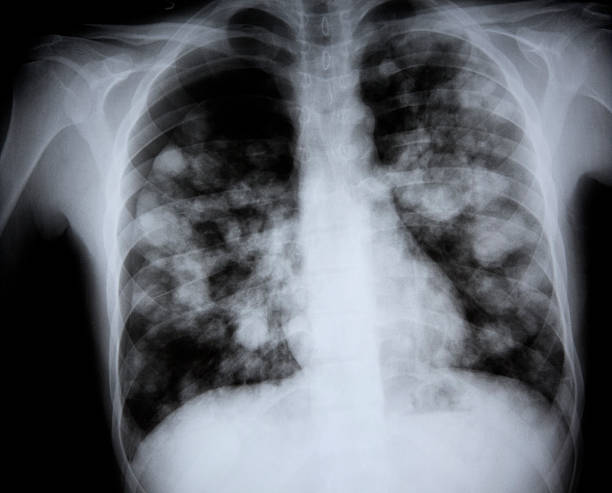

급성 폐렴은 폐의 염증으로 인해 발생하는 질병으로, 주로 세균, 바이러스, 곰팡이 등의 감염에 의해 유발됩니다. 이 질병은 폐의 공기 주머니인 폐포에 염증이 생겨 가스 교환이 원활하지 않게 됩니다. 급성 폐렴은 특히 면역력이 약한 노인이나 어린이에게 치명적일 수 있습니다.

급성 폐렴의 원인은 다양합니다. 가장 흔한 원인은 세균 감염이며, 특히 폐렴구균이 주요 원인균으로 알려져 있습니다. 그 외에도 인플루엔자 바이러스, 코로나바이러스, 아데노바이러스 등 다양한 바이러스가 급성 폐렴을 유발할 수 있습니다. 또한, 흡연, 음주, 만성 질환 등은 폐렴의 위험을 증가시킬 수 있습니다.